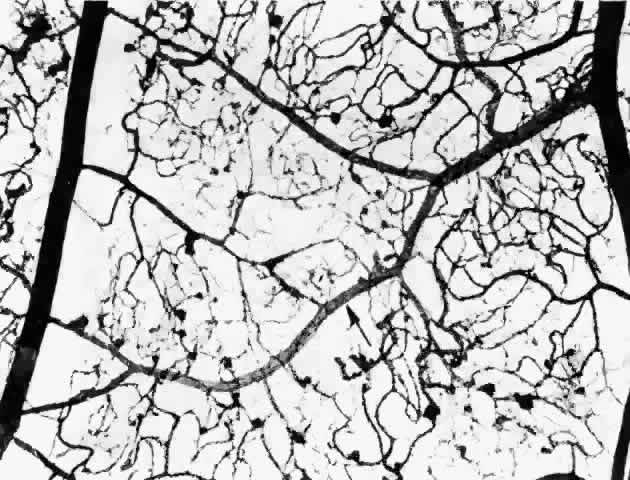

As shown by trypsin digestion, capillary pericytes are lost first,27 followed by endothelial cells (Figs. 6 and 7). Aldose reductase, one of the enzymes in the sorbitol metabolic pathway, is present in significant quantities in retinal capillary pericytes, but not in endothelial cells, and may thus be implicated in the formation of microaneurysms.37 The final result is an acellular segment of capillary that is nonperfused on fluorescein angiography.36

Fig. 6. Diabetic retinal capillary. A. Basement membrane shell (arrows) is the only remaining indication of where the pericytes had been. B. Nondiabetic normal capillary shows the basement membrane shell (arrow) around the pericyte. C. Diabetic capillary has only a basement membrane shell (arrow), with the nucleus absent. (A, PAS, × 630; B, PAS, × 850; C, PAS, × 630)

Fig. 7. Retinal capillary microaneurysm (RCM). A. RCMs occur in random distribution between the arteriole (a) and venule (v). “Young” RCMs are seen as saccular capillary outpouchings with proliferated endothelial cells (arrows). “Old” RCMs appear as solid black balls with their lumens obliterated by PAS-positive material. Note the darker color of the capillaries with thickened basement membranes and arteriolar-venular connections. B. Very large RCM (arrow) or the tiny hemorrhages associated with abnormal vessels are probably responsible for the RCMs seen clinically. (A, PAS, × 40; B, PAS, × 115)